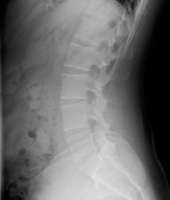

Позвоночника тред

Сап, медач. Есть спина пикрелейтед. Можно ли выпрямить и нужно ли? Алсо, была глрыжа диска L5-S1, успешно удалена. После этого невролог посоветовал врача лфк у которого этим всем заниматься, проблема в том, что это, сука стоит 3,5к (дс) за час, собственно вопрос, стоит ли? Нужно ли это и не разводят ли меня?